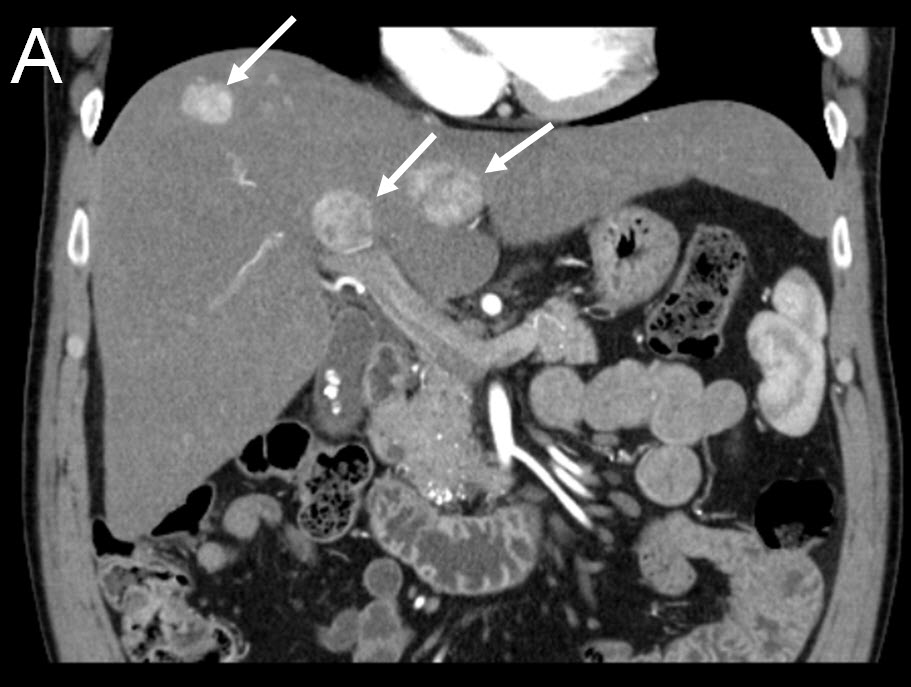

Treating Multiple Liver Tumors with Drug Eluting Beads (DEB TACE)

| (A) Coronal CT-scan of patient with multiple liver tumors |